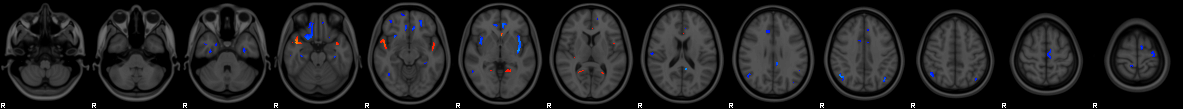

Prior:

1% weight

Thickness

4% weight

:

VBM

6% weight